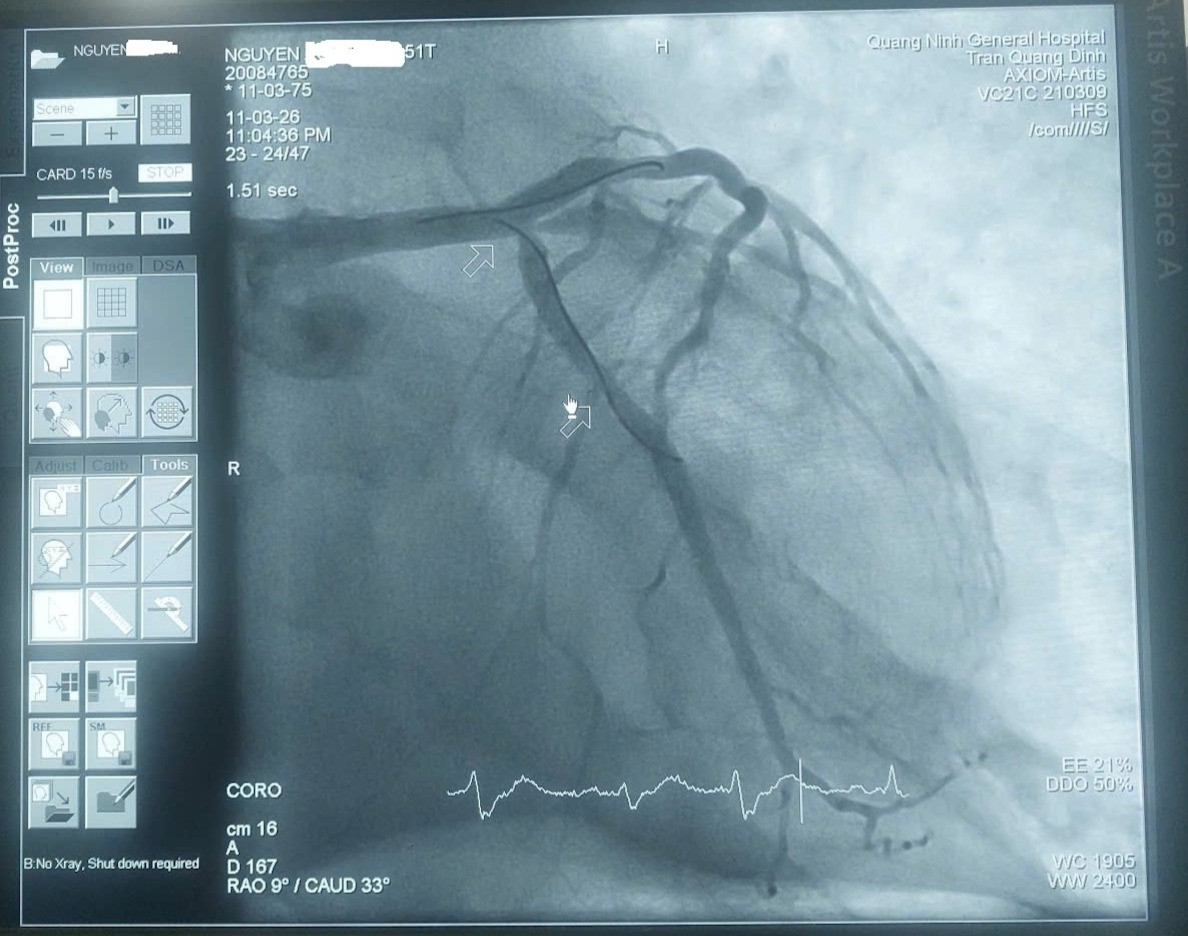

Kết quả chụp mạch vành cho thấy hẹp khít thân chung động mạch vành trái. Ê-kíp đã đặt một stent đoạn LM–LAD, các nhánh còn lại hẹp mức độ vừa và được điều trị nội khoa.